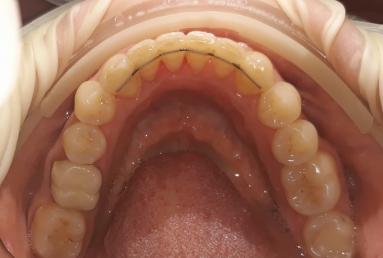

SAPPHIRE ORTHODONTIC DEVICE

Orthodontic treatment, external sinus lifting, dental implant and zirconium crown.